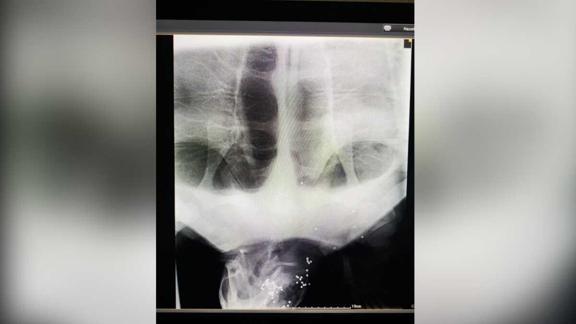

Burada veterinerlerce muayene edilen ve röntgeni çekilen 26 kilogram ağırlığındaki dişi kaplumbağanın, ateşli silahla vurulmuş olduğu belirlendi.

Kaplumbağanın ayrıca sol yüzgecinde 8 santimetre uzunluğunda derin bir yırtık, yüzünün sol tarafında 7 santimetre büyüklüğünde doku kayıplı bir yara, kabuğunda ise 4,5 santimetre uzunluğunda bir çatlak bulunduğu tespit edildi.